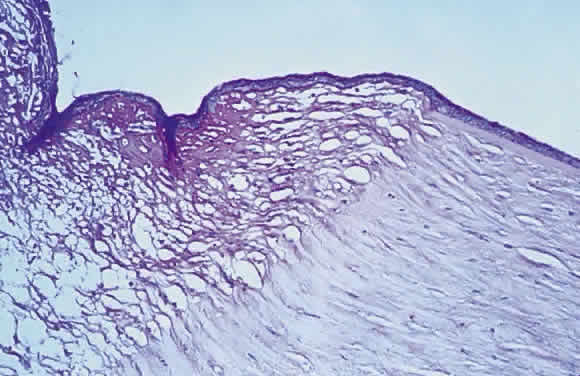

Epithelial changes consequent to vitamin A deficiency are equally well recognized but less well understood. Vitamin A is required for maintenance of normal epithelial architecture, particularly of mucous membranes. In its absence, keratinizing metaplasia occurs in a variety of organs.24 The conjunctiva, because of its accessibility, has been the best studied.23,25,26 Goblet cells are lost, and keratinized material, often containing numerous saprophytic organisms (especially the xerosis Bacillus, a gram-positive diphtheroid), covers the surface (Fig. 1). Below the keratinized surface is a thickened layer of flattened cells and, deep to this, a prominent granular cell layer. The architecture of deeper layers is moderately disorganized. A mild, chronic inflammatory infiltrate may be present in the substantia propria. Occasionally, in severe cases, rete pegs are present.27

Fig. 1. Histopathologic changes of conjunctival xerosis in a 25-year-old Indonesian woman. The epithelium is characterized by keratinization, a prominent granular cell layer, and distended squamous cells with large, open nuclei and prominent nucleoli. A mild mononuclear cell infiltrate, not apparent in this section, also was present. (H & E, × 700) (Sommer A, Sugana T, Djunaedi E, Green R: Vitamin A-responsive panocular xerophthalmia in a healthy adult. Arch Ophthalmol 96:1630, 1978)

Histopathologic material of mild corneal changes displays the same flattening and keratinization of epithelial cells.28